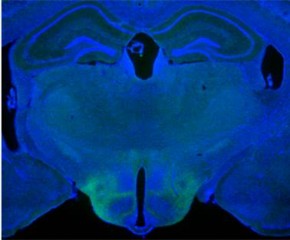

- ¡ã »çÁø=Æ÷Åä¾ÖÇÃ/¸ÞµðÆ÷Åä, ¿ÜÃø Á߰ݺ®

ºÐ³ë°¡ ¿ÜÃø Á߰ݺ®À̶ó´Â ³úÀÇ Æ¯Á¤ ºÎÀ§¿Í °ü·ÃÀÖ´Ù´Â ¿¬±¸°á°ú°¡ ³ª¿Ô´Ù.

´º¿å´ë ¶û°ï¸ÞµðÄü¾ÅÍ µå·òÄ˹з¯ ½Å°æ°úÇבּ¸¼Ò ¼ö¼®¿¬±¸ÀÚ ´ÙÀ¯ ¸°(Dayu Lin) ¹Ú»ç ¿¬±¸ÁøÀº ¿Ü°úÀûÀ¸·Î ¼öÄÆ ÁãÀÇ ³ú¿¡ ÇÁ·Îºê¸¦ »ðÀÔÇÏ¿© ³ú¼¼Æ÷ÀÇ ÀϺΠºÎÀ§¸¦ ÈïºÐ½Ã۱â À§ÇØ ±× ºÎÀ§¿¡ ºûÀ» ½î´Â ½ÇÇèÀ» ÇÏ¿© ÀÌ·¯ÇÑ °á°ú¸¦ ¾ò¾ú´Ù°í ¸ÞµðÄôº½ºÅõµ¥À̰¡ 12ÀÏ(ÇöÁö½Ã°£) º¸µµÇß´Ù.

¼öÄÆ ÁãÀÇ °©ÀÛ½º·´°í Æø·ÂÀûÀÎ ÇൿÀº ¿ÜÃø Á߰ݺ®(lateral septum)À̶ó´Â ³úÀÇ ±¸Á¶ º¯È¿Í ¿¬°üÀÖ´Ù´Â Á¡ÀÌ È®ÀεƴÙ.

¶Ç ¿¬±¸ÁøÀº ¿ÜÃø Á߰ݺ®ÀÇ Æ¯Á¤ ³ú¼¼Æ÷¸¦ Ȱ¼ºÈÇÏ¿© ½ÇÇèÁãÀÇ °ø°Ý¼ºÀ» ÀÏÀ¸Å°°Å³ª(½ºÀ§Ä¡ ¿Â) Â÷´Ü(½ºÀ§Ä¡ ¿ÀÇÁ)ÇÒ ¼ö ÀÖ´Ù´Â Á¡À» ¹ß°ßÇß´Ù.

¿¬±¸Àڵ鿡 µû¸£¸é ¿ÜÃø Á߰ݺ®Àº °¨Á¤°ú ÇнÀ°ú °ü·ÃµÈ ³ú ºÎÀ§ÀÎ ÇØ¸¶¿Í ¿¬°áµÇ¸ç È£¸£¸ó »ý»ó°ú °ø°Ý¼º°ú ¹ÐÁ¢È÷ °ü·ÃµÈ ³ú ºÎÀ§ÀÎ ½Ã»óÇϺηΠµ¹ÃâµÇ¾î ÀÖ´Ù.